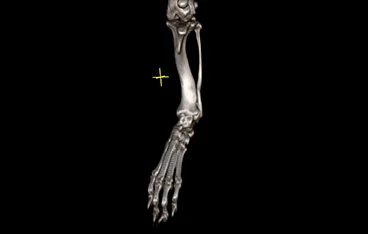

5. 단순한 교정을 넘어, 뼈 기형에 대한 근본적 접근

단순 교정이 아닌, 기형의 원인과 해부학적 구조를 바탕으로 3D 정밀 분석 후 맞춤형 치료를 진행합니다.

• 각기형(ALD)

• 각기형(ALD) 수술 전

각기형(ALD) 수술 후